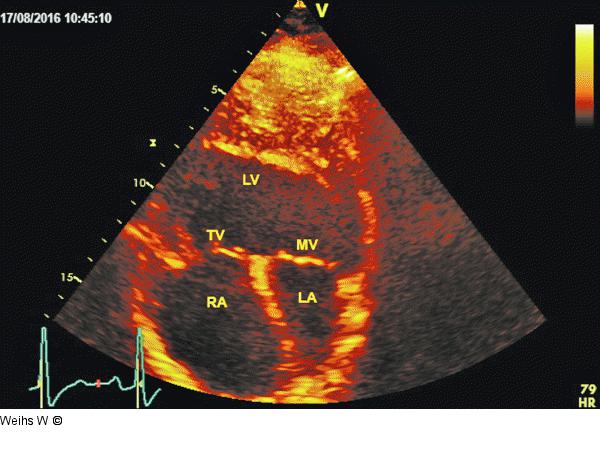

Abbildung 5: Apikaler Vierkammerblick Apikaler Vierkammerblick mit Darstellung des „double inlet single left ventricles“. LA: linker Vorhof; RA: rechter Vorhof; TV: Trikuspidalklappe; MV: Mitralklappe; LV: linker Ventrikel |

Apikaler Vierkammerblick mit Darstellung des „double inlet single left ventricles“. LA: linker Vorhof; RA: rechter Vorhof; TV: Trikuspidalklappe; MV: Mitralklappe; LV: linker Ventrikel |